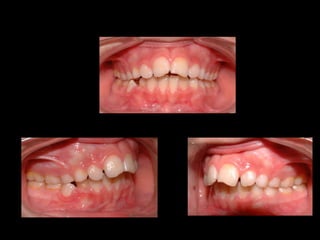

Rotación distal  del molar

BARRA PALATINA CORRIGIENDO LA ROTACIÓN MOLAR SE PUEDE GANAR 1-2 MM DE LONGITUD DE ARCADA POR LADO

ACTIVACIÓN DE ROTACIÓN DISTAL INSTALAR LA BARRA DE UN LADO EL OTRO EXTREMO DEBE QUEDAR 5MM POR DISTAL DEL TUBO CONTRARIO

LA ACTIVACIÓN  ES CORRECTA CUANDO LA LLAVE LIBRE  SE DESPLAZA  5MM  POR DISTAL DEL TUBO OPUESTO

BARRA PALATINA CORRIGIENDOLA ROTACIÓN MOLAR SE PUEDE GANAR 1-2 MM DE LONGITUD DE ARCADA POR LADO

ACTIVACIÓN DE ROTACIÓNDISTAL INSTALAR LA BARRA DE UN LADO EL OTRO EXTREMO DEBE QUEDAR 5MM POR DISTAL DEL TUBO CONTRARIO